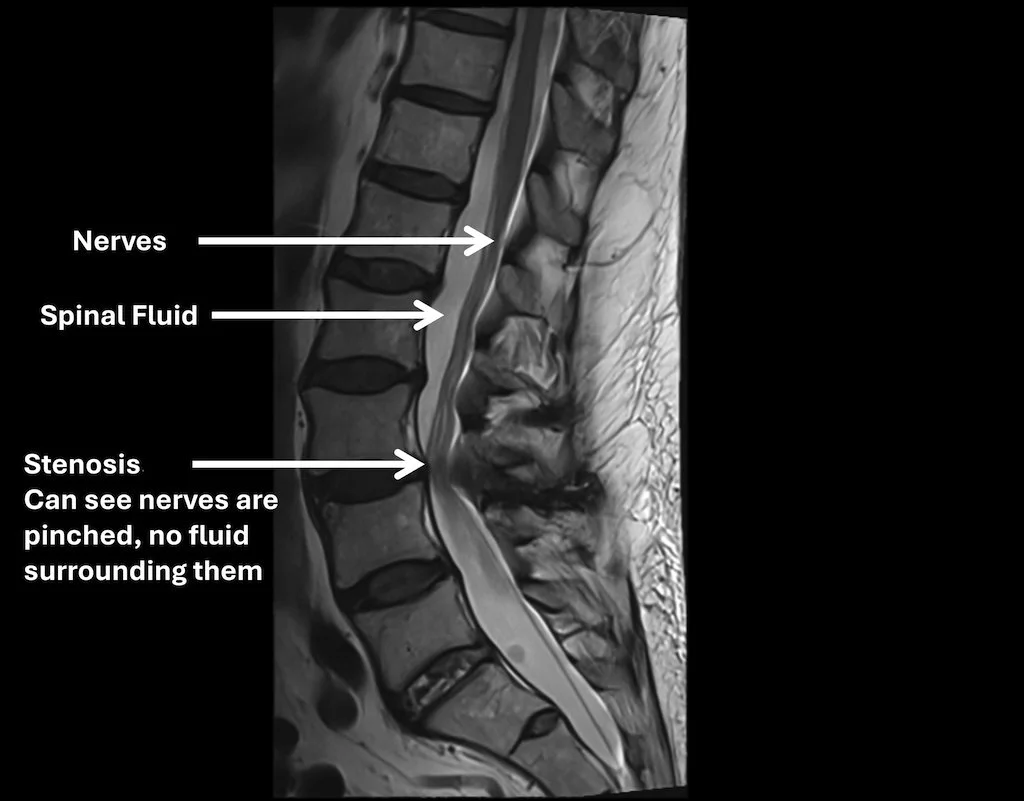

MRI scan of the lower spine showing nerves, spinal fluid, and stenosis. Nerves are pinched with no fluid surrounding them.

• MRI of the lumbar spine

MRI shows the spinal canal, discs, joints, and nerves clearly and helps identify areas of narrowing.

• MRI is helpful when symptoms persist or surgery is being considered.

• X-rays show bones but not discs or nerves.

However, X-rays are also important because they can show your bone alignment and possibly other issues that are not shown on MRI.

• Imaging must be interpreted together with your symptoms and exam.